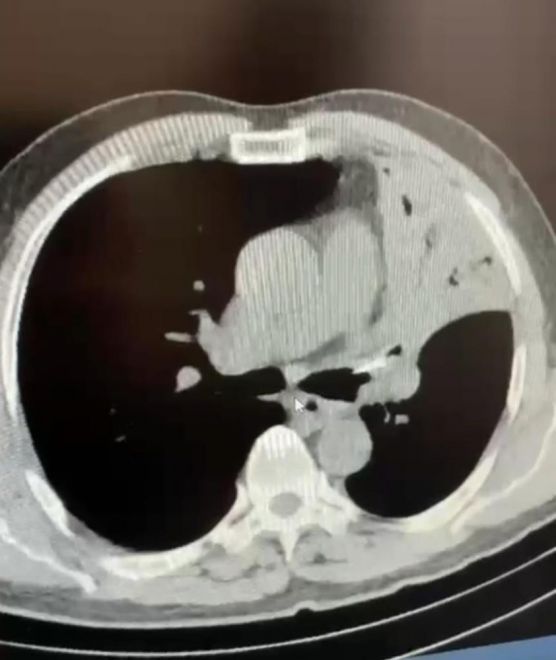

Edinilen bilgiye göre, Düzce’nin Cumayeri ilçesinde yaşayan Mehmet Salih Fer, uzun süredir devam eden öksürük ve şiddetli ağrı şikayetiyle AİBÜ İzzet Baysal Eğitim ve Araştırma Hastanesi’ne gitti. Fer’in yapılan muayenesinde sol akciğerine lades kemiği saplandığı tespit edildi. Fer’in 5 yıl boyunca akciğerinde saplanmış halde bulunan lades kemiği yapılan ameliyatla alındı. Sağlığına kavuşan Fer, yapılan son kontrollerinin ardından taburcu edildi.

5 yıl boyunca öksürük, şiddetli ağrı sırtında yanma şikayetleri bulunduğunu ifade eden Mehmet Salih Fer, “Aynı şikayetlerle hastanelere gittim, muayenelerim yapıldı, filmler çekildi. Sık sık enfeksiyon geçiriyordum, farklı farklı tanılar konuldu ve ilaç tedavileri başlatıldı. Ancak hiçbir sonuç alamadım ve şikayetlerim devam etti. Son olarak İzzet Baysal Eğitim ve Araştırma Hastanesi Göğüs Cerrahisi kliniğine geldim. Burada doktorlarım tarafından muayenelerim ve tetkik işlemlerim yapıldı. Neticede sol akciğerimde yaklaşık 5 senedir bir lades kemiği ile yaşadığımı öğrendim” dedi.